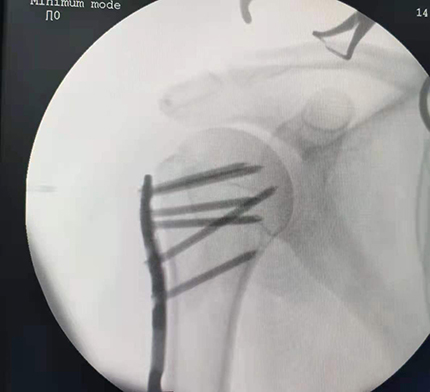

4月15日下午,敖先生在家人擔憂的目光下被快速推進手術室。骨科張廣院長淡定從容的消毒、切開皮膚、清理血塊及軟組織、螺釘固定患處、C臂透視觀察患處復位情況后縫合、消毒、止血以及包扎。一個半小時后,手術順利完成,僅傷口3-2厘米,術中幾乎無出血。

1621475867214450.jpg

1621475867175498.jpg